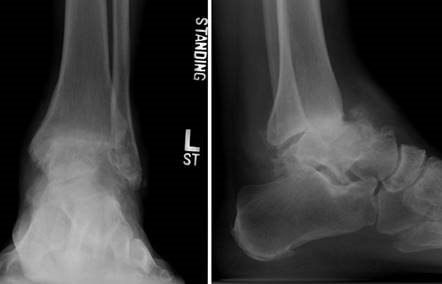

Weight-bearing anteroposterior (AP), lateral, and sesamoid axial radiographs are mandatory. On the AP view, the surgeon measures the Hallux Valgus Angle (HVA, normal < 15°), the Intermetatarsal Angle (IMA, normal < 9°), and the Distal Metatarsal Articular Angle (DMAA). The lateral view is scrutinized for Meary's angle (talo-first metatarsal angle) to identify midfoot collapse, as well as the presence of dorsal osteophytes indicative of hallux rigidus. The sesamoid axial view is critical for assessing the degree of sesamoid subluxation and the integrity of the crista.

Clinical & Radiographic Imaging Archive